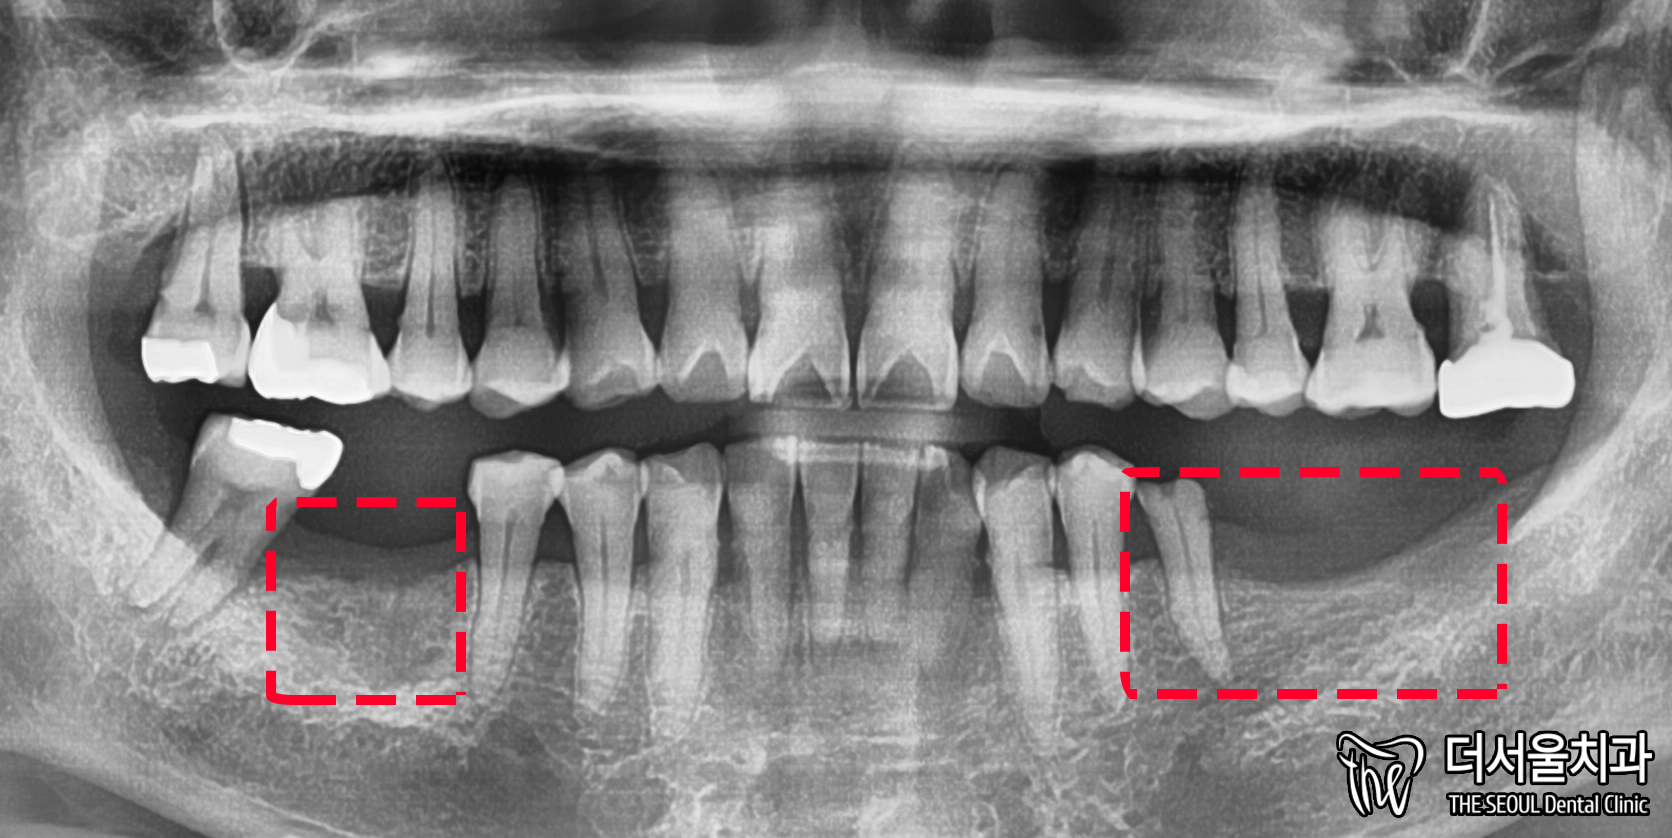

환자분 구내는 어떤 상태일까요?

성남 치과 의원은 먼저 눈으로 살펴봤습니다.

아래를 보면 36, 37, 46번 어금니가 없네요.

그런데 35번은 또 치근만 남아있습니다.

발치할 수밖에 없겠네요.

또, 잇몸뼈가 많이 없습니다.

얇아진 부분을 볼 수 있죠?

아마 치아가 없어진지 오래 되었을 겁니다.

여쭤봤는데 10년이나 두고 있으셨네요.

좀 더 자세히 체크하기 위하여

엑스레이를 찍어봤습니다.

높이는 그렇게 내려가지 않은 것으로 보여집니다.

다만, 너비가 줄어들었던거죠.

아래 임플란트 수술 시,

꼭 주의해야 되는 하치조신경관.

이것과 가깝지는 않은 듯 보였습니다.